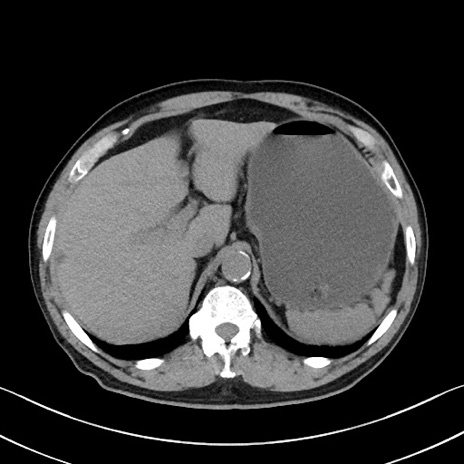

症例35(横断像)

【症例】70歳代 男性

【主訴】腹部膨満、嘔吐

【現病歴】昨日より腹部膨満感出現。本日増悪し、仙痛出現。嘔吐あり、受診。

【既往歴】糖尿病、胆摘後

【身体所見】BP 149/80mmHg、HR 74/min、BT 35.9℃、腹部:膨満、軟、圧痛なし。腸雑音減弱あり。上腹部正中切開瘢痕あり。

【データ】WBC 13500、CRP 1.72